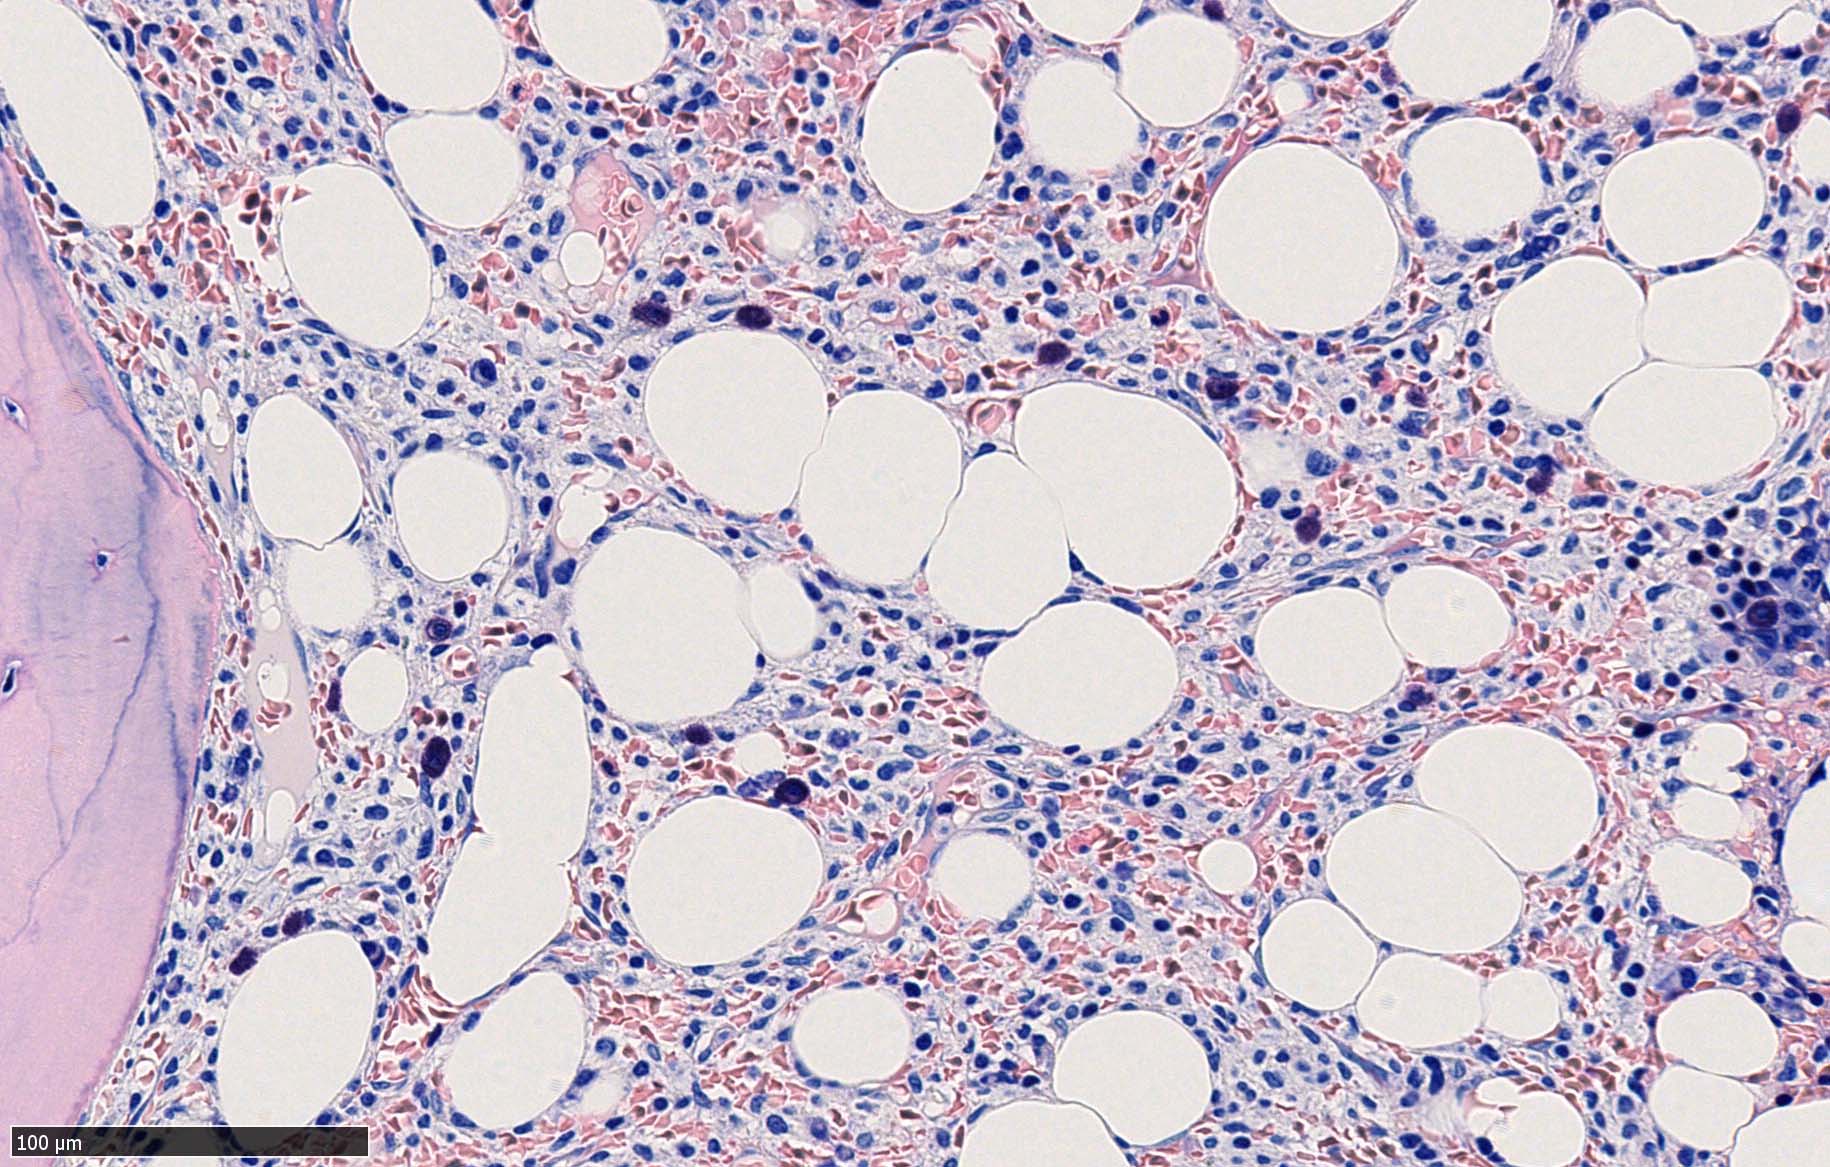

ASD-Giemsa陰性の細胞がシート状に増殖する. 核はクロマチン濃染, 核小体は不明瞭.類円形, 卵円形, くびれを持つ多稜形核, 長円形いびつで屈曲した核, など多彩. 細胞質は淡清色調, 広く淡明. 赤芽球血島は幼若赤芽球のみで形成される異形成像を示す. やや離れて成熟赤芽球が疎な集簇を示す.

Immunophenotype

骨髄生検組織を使ったFCMのため, 細胞数が少数であるがCD19, CD20陽性のB-cellが優位で, lambda LC > kappa LCの偏倚がみられclonalな増殖が考えられる. B-cellはCD11c, CD25も発現している. Hairy cell leukaemiaが疑われる. CD103はこのFCMセットには組み込みがなかった.

Hairy-FCM のコピー.jpg ASD-up-PAX5ok.jpg びまん性にPAX5陽性の小型B-cellsが増殖している.

増殖細胞はCD20(相変わらずべったり染まる), CD19, PAX5陽性 CD25陽性.